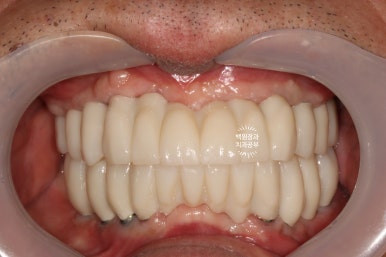

그리하여 완성된 최종보철물입니다!!

옛날부터 임플란트 틀니용으로 사용하시던 임플란트 3개는 임플란트 주위염이 조금 있어 약~간 쇠기둥 색깔이 보인다는 단점이 있긴 하지만, 다른 임플란트들은 꽤나 예쁘게 제작이 되었네요.

위 아래 교합면 사진을 보시면, 과연 이게 임플란트인가? 싶으실거에요. 치아에 지르코니아 크라운을 붙인 것과 큰 차이를 못느낄 정도로 정말 자기 치아같이 예쁘게 제작된 임플란트 크라운을 보실 수 있습니다!!